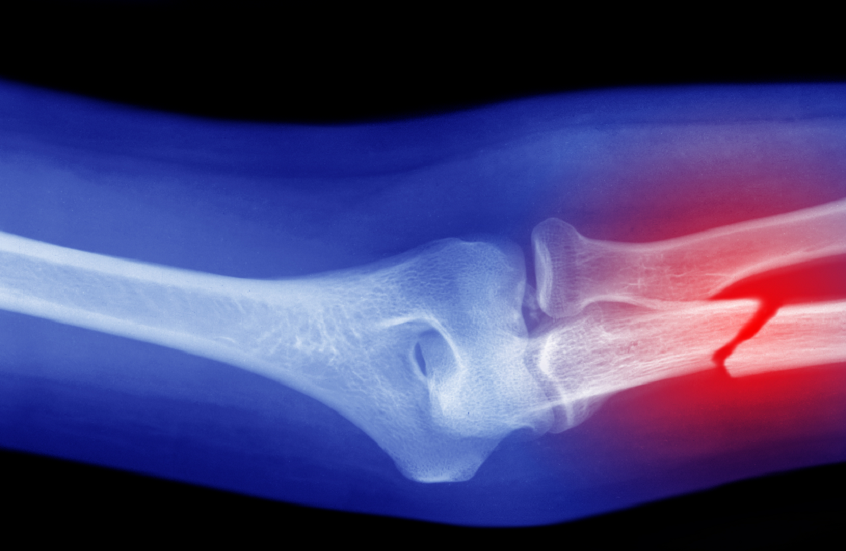

طوّر باحثون صينيون طريقة جديدة تساعد على الكشف عن مشاكل هشاشة العظام في الجسم.

وأشارت مجلة Frontiers in Endocrinology إلى أن الباحثين في جامعة تشونغتشينغ الطبية الصينية اقترحوا استخدام مؤشر مستوى أنزيم الفوسفاتاز القلوي الكلي في الدم كطريقة منخفضة التكلفة للكشف عن ارتفاع خطر الإصابة بهشاشة العظام، وبينت نتائج دراستهم أنه حتى مع القيم “الطبيعية” للإنزيم، فإن الارتفاعات الطفيفة أكثر شيوعا بشكل ملحوظ لدى الأشخاص الذين يعانون من انخفاض كثافة المعادن والعناصر في العظام.